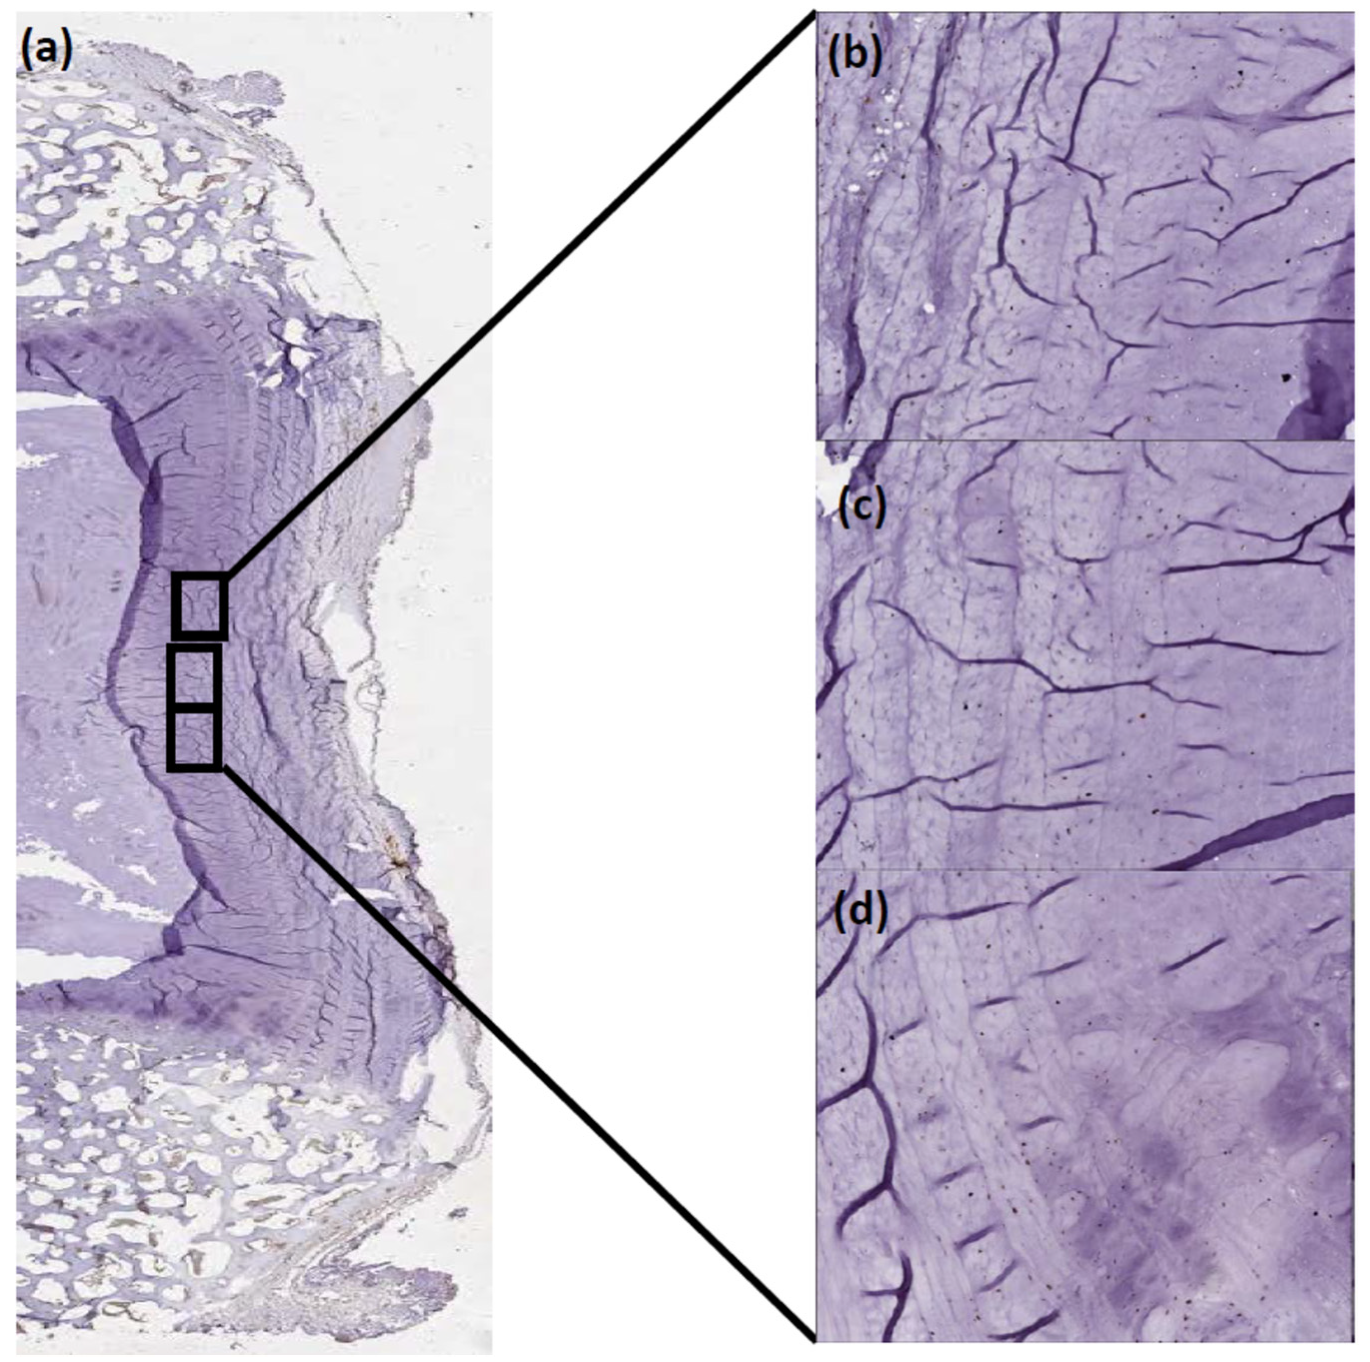

4.2. Tissue Preparation

Immunohistochemistry (IHC)